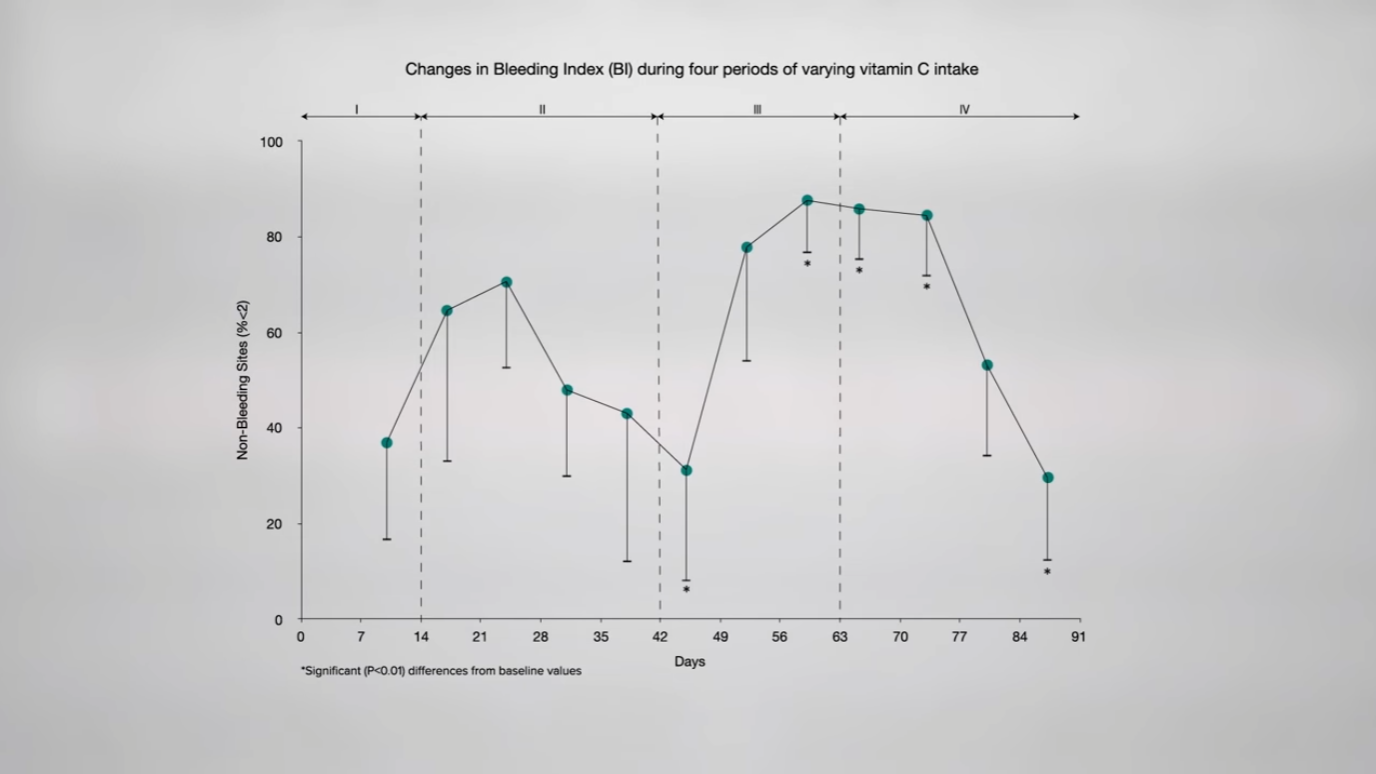

Is there an association between periodontitis and dietary vitamin C intake? Apparently so, as you can see in the graph below and at 3:34 in my video. Increased risk of periodontitis has been associated with lower levels of vitamin C intake. What effect might vitamin C depletion and supplementation have on periodontal health? Researchers provided controlled amounts of vitamin C to study participants for three months and found that measures of gum inflammation were directly related to the subjects’ vitamin C status. On about one orange’s worth of vitamin C a day, their gums improved; down around only 5 mg a day, though, their gums got worse. On ten oranges’ worth of vitamin C a day, they got better and then worse once again when the vitamin C level dropped down to five oranges’ worth, as you can see in the graph below and at 4:01 in my video. The study was pretty convincing, though 5 mg a day is down at scurvy level. We know our gums start bleeding and our teeth can fall out if we have scurvy, but that doesn’t mean taking extra vitamin C helps.